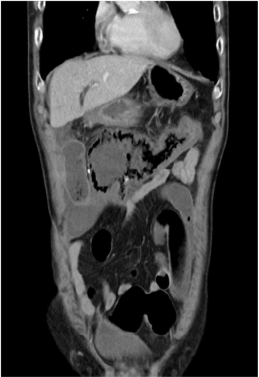

85세 남자가 4시간 전부터 혈변을 본다고 병원에 왔다. 30년 전부터 고혈압, 당뇨병으로 진단받고 약물을 복용 중이다. 식후 갑작스러운 복통이 생겼고 1시간 뒤 점액이 섞인 혈변을 보았다고 한다. 혈압 150/90 mmHg, 맥박 96회/분, 호흡 22회/분, 체온 37.9°C이다. 배는 팽만하고, 배 전체에 압통이 있으나 반동압통은 없다. 복부 컴퓨터단층촬영 사진이다. 진단은?

CT: Ascending colon wall thickening with nearby fluid collection, SMA stenosis/occlusion

고혈압 및 당뇨 기저질환을 가진 고령환자에게서 급성 복통 및 혈변이 발생하였으며, CT상 SMA stenosis/occlusion이 확인되므로 ischemic colitis로 진단한다.

• 혈액검사 결과 leukocytosis 및 CRP/ESR elevation 소견은 환자에게 염증성 병변이 발생했음을 시사하며, 복부 CT상 SMA의 near-total occlusion이 확인되고, SMA가 주된 혈류를 담당하는 ascending colon의 wall thickening과 주변 fluid collection이 허혈대장염이 적절한 진단명일 가능성이 높다.